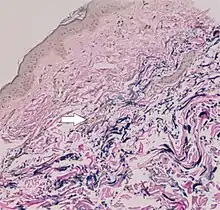

In PXE, there is mineralization (accumulation of calcium and other minerals) and fragmentation of the elastin-containing fibers in connective tissue, but primarily in the midlaminar layer of the dermis, Bruch's membrane and the midsized arteries.[26] Recent studies have confirmed that PXE is a metabolic disease, and that its features arise because metabolites of vitamin K cannot reach peripheral tissues.[27] Low levels of PPi cause mineralization in peripheral tissues.[19]

The diagnostic criteria for PXE are the typical skin biopsy appearance and the presence of angioid streaks in the retina. Criteria were established by consensus of clinicians and researchers at the 2010 biennial research meeting of the PXE Research Consortium.[29] and confirmed at the 2014 meeting[30] These consensus criteria state that definitive PXE is characterized by two pathogenic mutations in the ABCC6 or ocular findings – angioid streaks > 1 DD or peau d’orange in an individual <20 years of age together with skin findings:

- Diagnostic histopathological changes in lesional skin: Calcified elastic fibers in the mid and lower dermis, confirmed by positive calcium stain

| Pseudoxanthoma elasticum | LM: Mid-dermal calcification and fragmentation of elastic fibers EM: Mineralization in elastic fiber core |